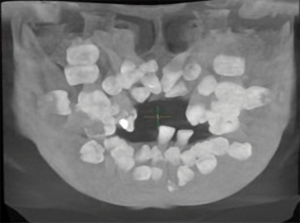

Segundo o que afirmam os pesquisadores Anand Marya, Adith Venugopal e Nikhilesh Vaid, a descoberta da variante extremamente rara da doença de Pierre-Marie e Santon se deu após a procura de um paciente do sexo masculino, de 15 anos, que se queixava da falta de dentes em ambas as arcadas.

Ao jovem paciente, que não havia tido um diagnóstico prévio, foi confirmada a presença de um distúrbio genético autossômico dominante raro. A detecção dessa variante rara só foi possível após a realização de exame clínico, imagens em 3D e de análise de DNA.